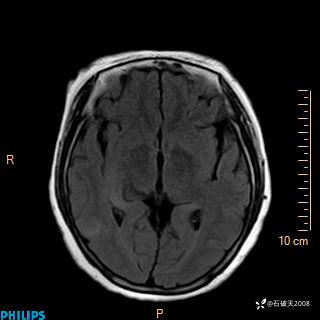

颅内占位,影像征象不是很丰富,有病理

hyy838 推荐女 62岁 主 诉:头晕12小时,加重1小时。

现病史:患者于12小时前无明显诱因出现头晕,呈持续性,无天旋地转及行走不稳,伴恶心、呕吐,呕吐共5次,呕吐物为胃内容物(具体性质不详),无胸闷、胸痛、心慌,无腹痛、腹泻,无咳嗽、咳痰,无发热、意识不清、肢体抽搐及大小便失禁等,1小时前患者上述症状加重,未诊疗,为求进一步治疗急自行来我院,门诊以“头晕待查”为诊断收入我科,发病来,神志清,精神差,饮食、睡眠差,大小便正常,体重未见明显下降。

T1